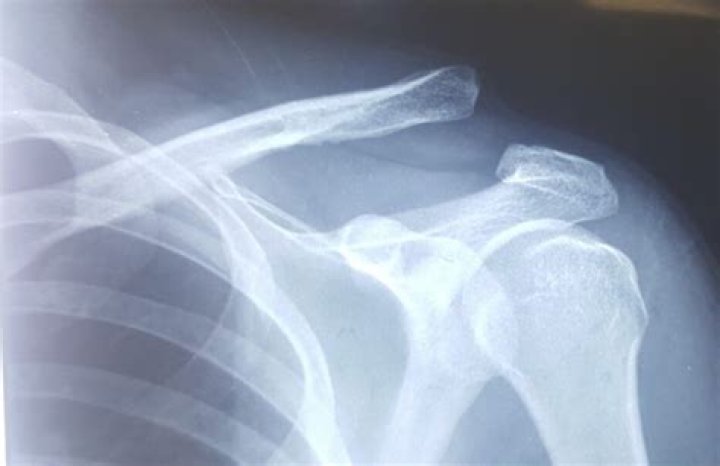

Can A Chiropractor Fix A Dislocated Clavicle?

Can you pop your clavicle out of place?

An AC joint injury, also known as a shoulder separation, is a common complication of dislocating the lateral end (outer) of the collarbone. Unfortunately, dislocation of the collarbone’s medial end (the part near your sternum-breastbone) is an extremely rare injury.

Does a dislocated collarbone hurt?

The dislocated end of the clavicle is usually visible in an anterior SC dislocation. This area is inflamed and hurts.